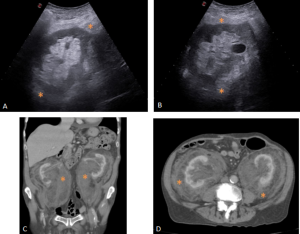

ULTRASONOGRAPHY (US)

RPF is visualized as a hypo or anechoic, irregular demarcated retroperitoneal mass, anterior to the lower lumbar spine or the promontory of the sacrum.

If ureteral entrapment is present, ureterohydronephrosis may occur in varying degrees.

MULTIDETECTOR COMPUTED TOMOGRAPHY (MDCT)

RPF typically appears as a well-defined, irregular paraspinal soft-tissue mass, isodense to the psoas muscle and without lateral extension beyond it. Most often centred at L4–L5 near the aortic bifurcation, it may extend cranially towards the renal hila or, less commonly, caudally to involve pelvic structures. Baseline Hounsfield units (HU) values and the diameter of the retroperitoneal tissue can assist in assessing inflammatory activity. [1,3,5-8]